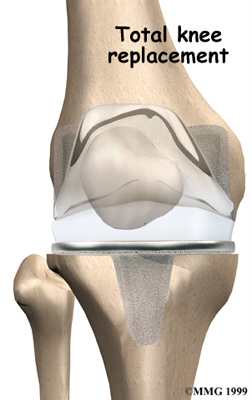

Artificial Knee Replacement

An artificial knee replacement is the ultimate solution for advanced knee OA.

Surgeons prefer not to put a new knee joint in patients younger than 60. This is because younger patients are generally more active and might put too much stress on the joint, causing it to loosen or even crack. A revision surgery to replace a damaged prosthesis is harder to do, has more possible complications, and is usually less successful than a first-time joint replacement surgery.

Related Document: FYZICAL Mechanicsburg's Guide to Artificial Joint Replacement of the Knee